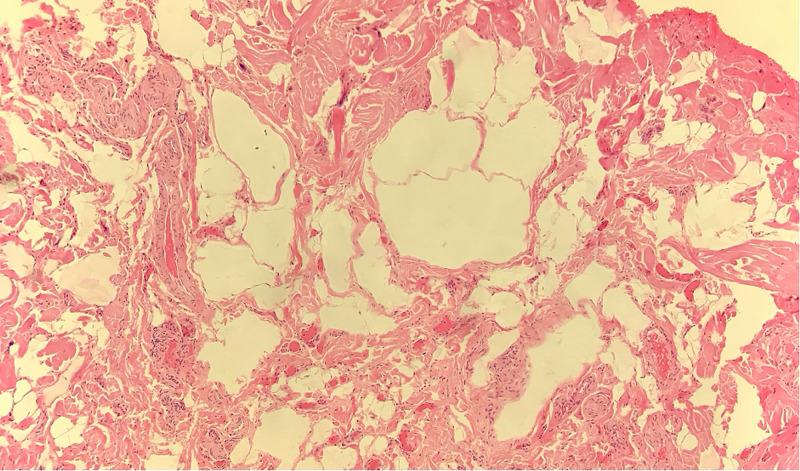

Administration of hyaluronic acid (HA) filler for aesthetic lip augmentation is a routine and common procedure with a low rate of adverse reactions. This case report documents an extremely rare complication of lip augmentation with HA leading to the development of lymphangiomas. Lymphangiomas are uncommon hamartomas of the lymphatic system. Although usually congenital, they can be acquired due to trauma, inflammation, or lymphatic blockage. They may be in the deep or superficial tissues, with superficial forms being either lymphangioma circumscriptum or acquired lymphangioma, also referred to as lymphangiectasia. Acquired lymphangiomas are typically formed by blockage of lymphatic drainage leading to dilation of the lymphatic channels. The diagnosis in our case report is acquired lymphangioma. A 27-year-old female presented with a two-year history of linear swellings in her upper lip. These lumps followed the line where HA filler had been injected four years earlier. Hyaluronidase had previously been used unsuccessfully to remove these lumps. The patient was treated with surgery to excise the lesions. Five masses were excised, and histopathological analysis displayed the presence of variably ectatic lacunae, lined by cells with CD34 expression, a lymph-vascular-endothelial marker. There were also scattered macrophages with CD68 expression in the interstices. These are typical features of a lymphangioma. The patient was satisfied with the excellent aesthetic and functional outcome. To our knowledge this is the first case of a lymphangioma following HA lip augmentation. Although rare, this complication can have aesthetic implications for the patient which may require further treatment or surgery to correct.

注射透明质酸(HA)填充剂进行唇部美容增大是一种常规且常见的手术,不良反应发生率较低。本病例报告记录了HA唇部增大极其罕见的并发症,导致淋巴管瘤的发生。淋巴管瘤是淋巴系统罕见的错构瘤。虽然通常是先天性的,但也可因创伤、炎症或淋巴阻塞而获得。它们可能位于深部或浅部组织,浅部形式为局限性淋巴管瘤或获得性淋巴管瘤,也称为淋巴管扩张症。获得性淋巴管瘤通常是由淋巴引流受阻导致淋巴管扩张形成的。我们病例报告中的诊断为获得性淋巴管瘤。一名27岁女性,上唇出现线状肿胀已有两年。这些肿块沿着四年前注射HA填充剂的线路分布。此前曾使用透明质酸酶试图消除这些肿块,但未成功。患者接受了手术切除病变。切除了五个肿块,组织病理学分析显示存在不同程度扩张的腔隙,内衬表达CD34的细胞,CD34是一种淋巴管内皮标志物。间隙中还散在有表达CD68的巨噬细胞。这些是淋巴管瘤的典型特征。患者对良好的美学和功能效果感到满意。据我们所知,这是HA唇部增大后发生淋巴管瘤的首例病例。尽管罕见,但这种并发症可能对患者的美观产生影响,可能需要进一步治疗或手术来纠正。